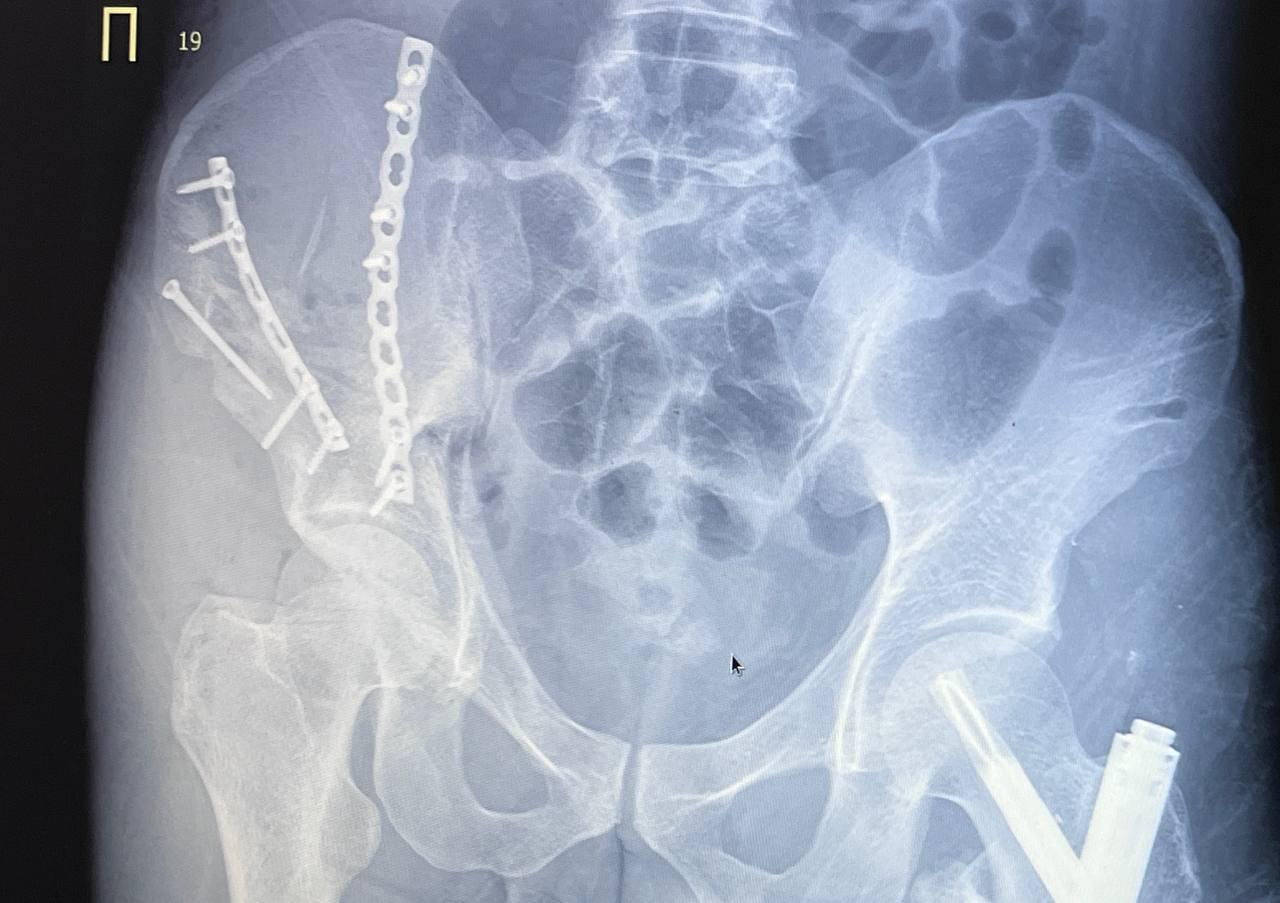

Спасли после падения с четвёртого этажа пациента травматологи больницы скорой помощи им. Подгорбунского

Тазовые кости мужчины практически полностью раздробились. Левое бедро закрепили штифтом, правую часть таза собрали по кусочкам за три операции. Сейчас мужчина идёт на поправку.